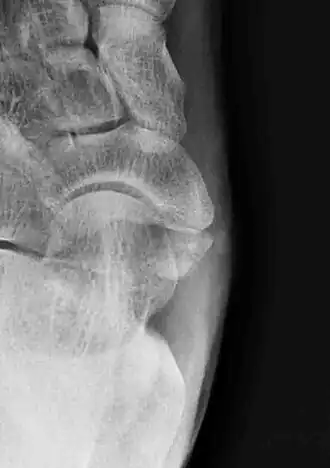

Os tibiale externum (met "externum" hier in de betekenis van mediaal gelegen) is de term die gebruikt wordt voor botjes bij de tuberositas van het os naviculare, dicht bij de pees van de musculus tibialis posterior.[1] Het botje werd voor het eerst beschreven in 1605 door Bauhin.[2] Ondanks de overeenkomstige ligging, is het niet gelijk aan het os sesamoideum tibialis posterioris.[3] Het is meestal achter de tuberositas van het os naviculare gepositioneerd, soms mediaal ervan. Tot dusverre zijn drie verschillende types van het os tibiale externum beschreven.[4] Type I is een waar sesambeentje, type II oogt als een niet-gefuseerd ossificatiepunt. Als het met het os naviculare gefuseerd is, wordt het os naviculare cornutum of scaphoïde débordant genoemd; dit is een os naviculare accessorium type III.[1]

Op röntgenfoto's wordt een os tibiale externum als incidentele bevinding soms onterecht aangemerkt als afwijkend, losliggend botdeel of als fractuur.[6] Met name verwarring met een avulsiefractuur van de tuberositas van het os naviculare treedt geregeld op. Een os tibiale externum is meestal groter en heeft een gladder botoppervlak dan een ware avulsiefractuur.[4] Een groot os tibiale externum wordt soms verward met een os sustentaculum tali. Een os tibiale externum bipartitum is een zeldzame vorm van een os tibiale externum dat uit twee delen bestaat.[6]